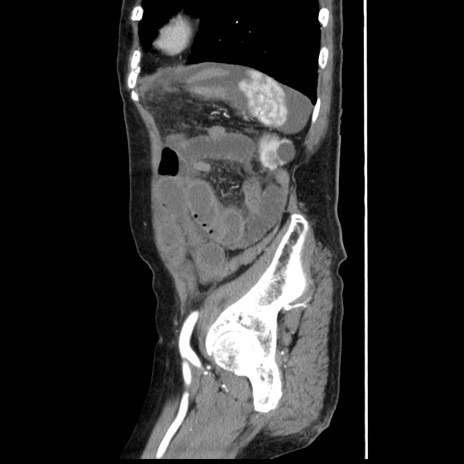

冠状断像

【症例】80歳代女性

【主訴】腹痛

【現病歴】8時間前から腹痛あり来院。

【既往歴】糖尿病、脂質異常症、子宮体癌にて子宮全摘術

【身体所見】意識清明・会話良好だが腹痛で苦悶様、全腹部にわたって反跳痛と圧痛あり

【データ】WBC 13600、CRP 0.14、LDH 224、CK 90